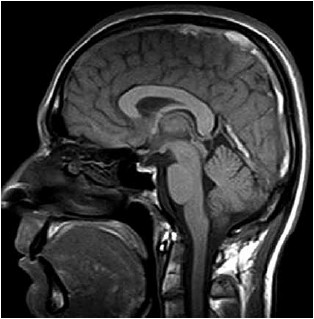

Mulher de 23 anos com 14 semanas de gestação relata quadro de cefaleia holocraniana há uma semana, que vem piorando de intensidade. A dor de cabeça piora à noite e causa visão embaçada. O exame clínico é normal e não há déficit neurológico focal, nem rigidez de nuca. Exames séricos são normais. A ressonância magnética T1 sagital realizada é mostrada a seguir:

(Arquivo pessoal; imagem usada com autorização)